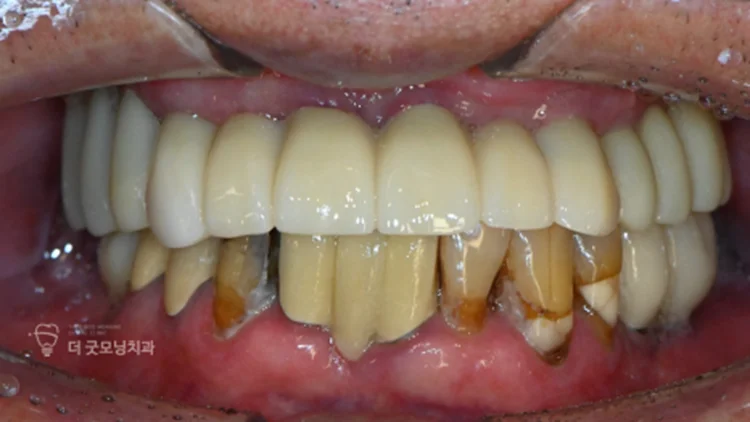

최종 결과 — 치료 전후 비교

치료 기간을 전략적으로 나누고 보험을 적극 활용함으로써, 총 11개 중 8개의 임플란트를 보험으로 처리하여 경제적 부담을 크게 줄일 수 있었습니다.

* 본 사례는 해당 의료기관에서 실제 진료를 받은 환자이며, 전후 사진은 동일인으로 촬영 시기 2024.09.05 ~ 2026.01.10, 별도 조작 없는 동일 조건 촬영 사진입니다.